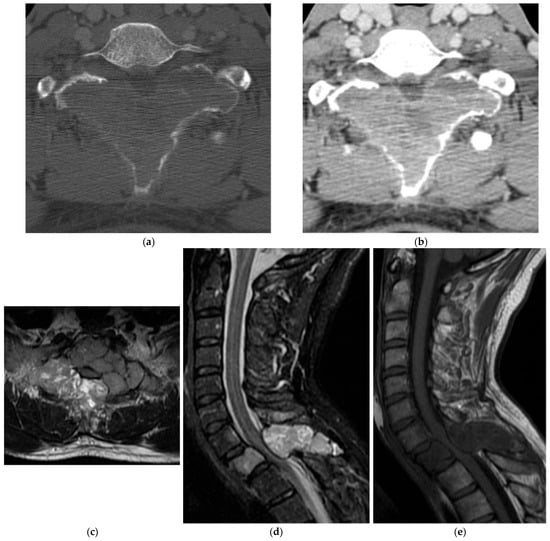

2.2. Chondrogenic

2.2.1. Osteochondroma

2.2.3. Chondrosarcoma

2.3. Notochordal